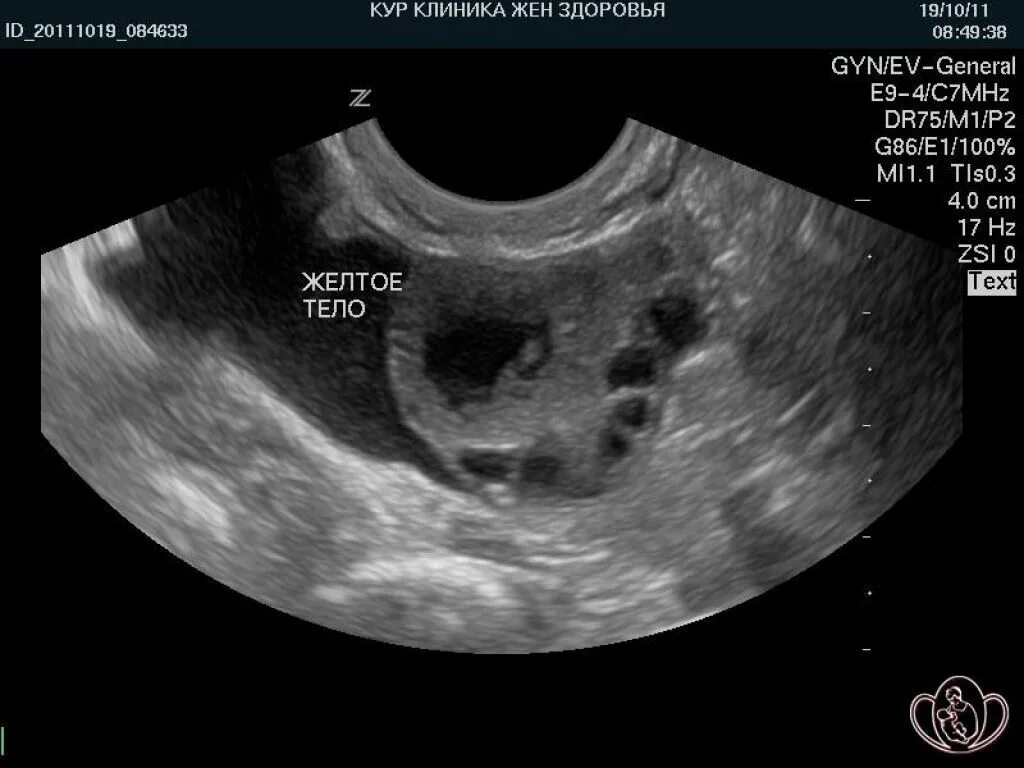

Фолликул после овуляции